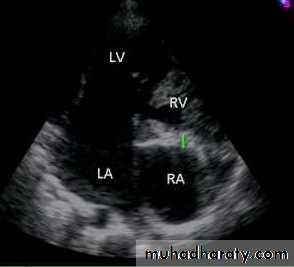

Ebstein anomaly consists of downward displacement of an abnormal tricuspid valve into the right ventricle.Pathophysiology

The right ventricle is divided into 2 parts by the abnormal tricuspid valve: the 1st, a thin-walled “atrialized” portion, is continuous with the cavity of the right atrium; the 2nd, often smaller portion consists of normal ventricular myocardium.

RV output is decreased due to a combination of the poorly

functioning small right ventricle and tricuspid valve regurgitation,

Echo is diagnostic and shows the abnormalities.